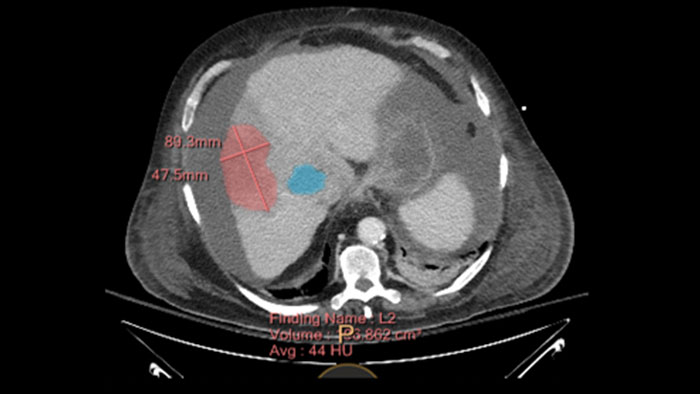

Semi-automatic tumor quantification

This semi-automated 3D (Volumetric) tumor response assessment tool, based on EASL (European Association for the Study of the Liver) criteria incorporates functional information from contrast-enhanced scans.

Benefits